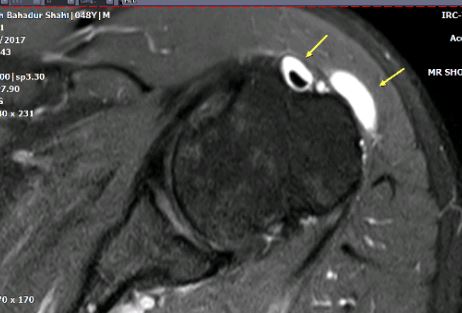

Sub Acromial Bursitis MRI. gan

Shoulder Ganglion

Ganglion with Intrarticular Extension